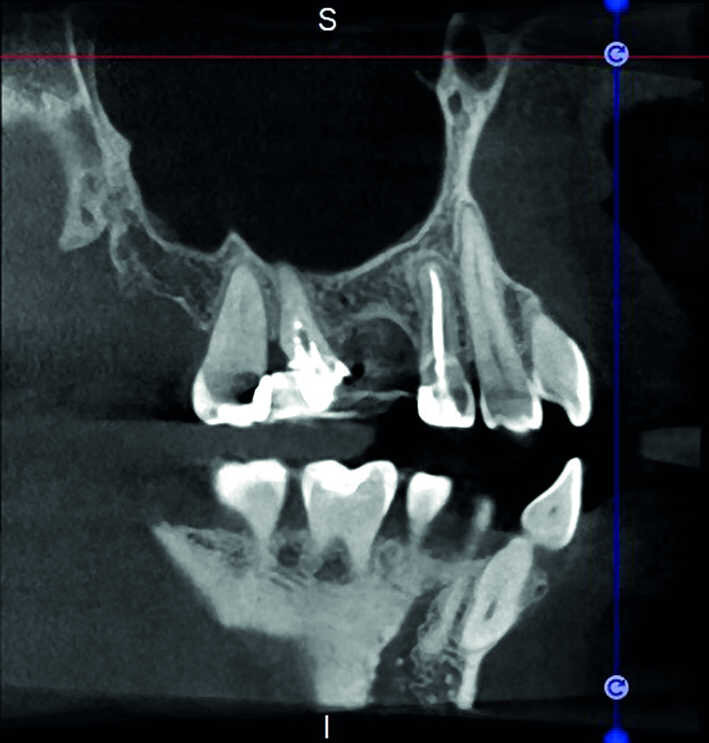

L’évaluation CBCT préopératoire est utile dans les cas nécessitant une approche chirurgicale, non seulement pour confirmer la présence d’une lésion, mais aussi pour planifier l’intervention et, en particulier, identifier le type d’incision chirurgicale à pratiquer, en fonction de la taille et de l’emplacement de la lésion en question (Figs. 23–25). Le cas spécifique présenté dans cet article est caractéristique de cette situation. La radiographie intraorale n’a pas permis de déterminer l’étendue de la lésion, qui touche non seulement la région apicale de la prémolaire, mais aussi un segment édenté en distal. Cette région doit faire l’objet d’un traitement régénérateur, afin de garantir la cicatrisation appropriée de la zone, suivi par la mise en place d’une membrane. Une approche totalement différente de celle requise pour la chirurgie endodontique doit être utilisée pour protéger le lambeau. Les différentes étapes de l’intervention sont illustrées dans les images peropératoires (Figs. 26–28). L’examen CBCT réalisé 12 mois plus tard, confirme la cicatrisation complète de la lésion apicale et la parfaite intégration de la greffe (Figs. 29–31).